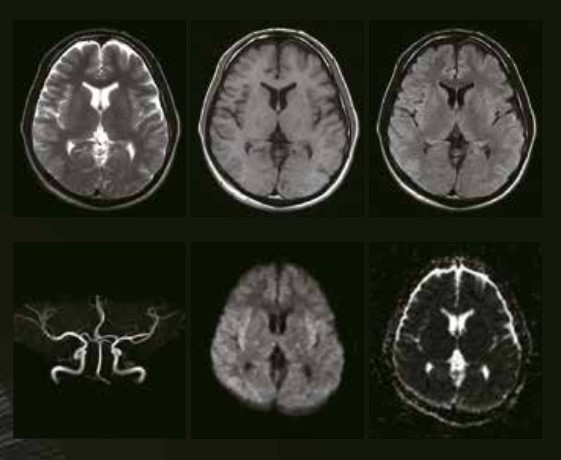

MRIは強い磁石と電波によって、身体の内部情報を画像化する検査で、Magnetic Resonance Imaging(磁気共鳴画像)の略です。レントゲン検査やCT検査とは異なり、放射線は使用しないため、被ばくの心配はありません。脳の形態や機能を調べることができます。脳卒中やがんなどの腫瘍がないかを調べることができ、認知症の原因検査にも有用です。脳の血管や神経の走行など細かな領域も評価が可能です。

従来のオープン型MRIでは、トンネル型と比べて低磁場であるため、どうしても画質が低下してしまうことが問題でした。しかし、当機器はAI技術を活用したSynergyDriveによって、通常の診療・診断に支障のないレベルの高画質を実現します。

近年、MRIにおいて注目されている高速化ソリューションの搭載が実現し、アンダーサンプリングと繰り返し再構成によって、画質を維持したままの短い撮像時間を実現しています。